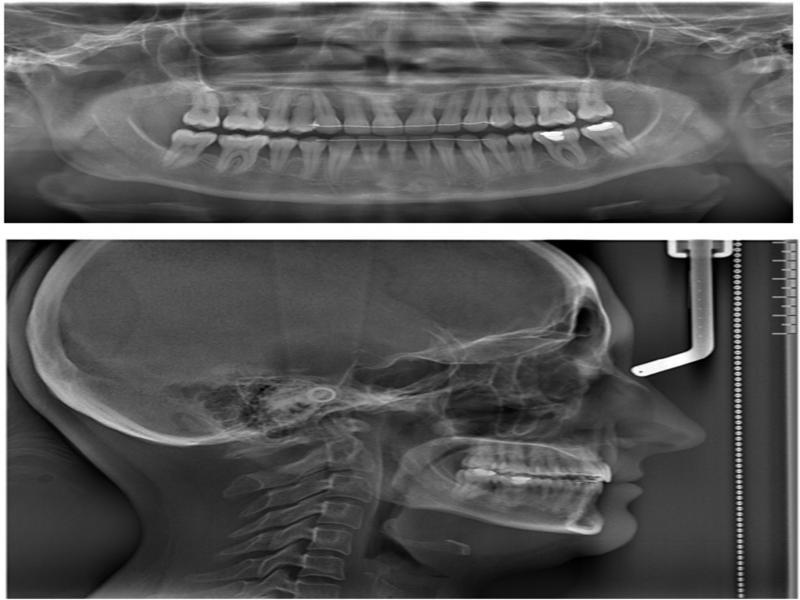

Figure 2.

Figure 3.